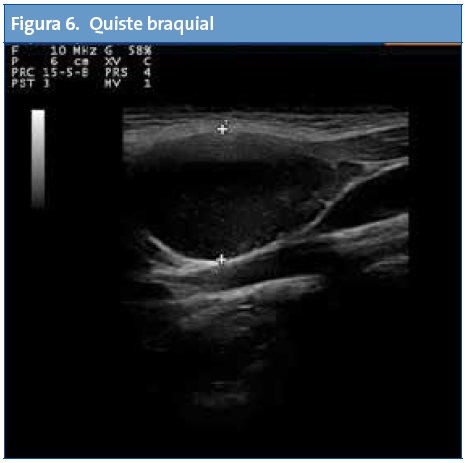

En Atención Primaria el mayor rendimiento se obtiene de la exploración abdominal seguida del estudio de la zona cervical, partes blandas, aparato genital, pulmón y aparato locomotor.